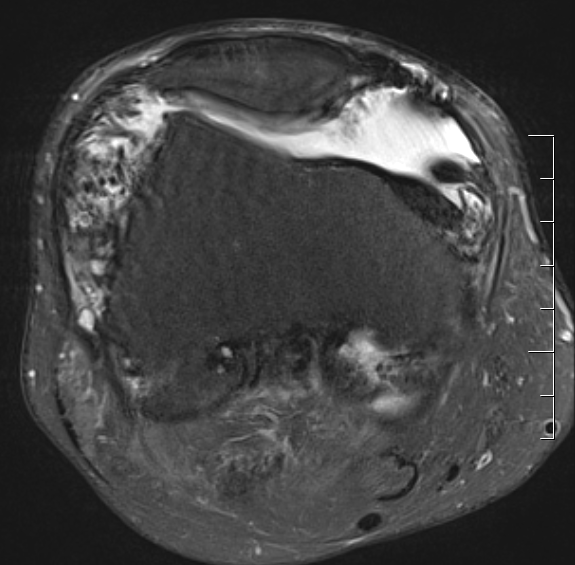

MRI

Synovial thickening

Hemosiderin

- low signal intensity on TI and T2 - "drop out" signals

- blooming on gradient echo

Severe diffuse PVNS with bony involvement